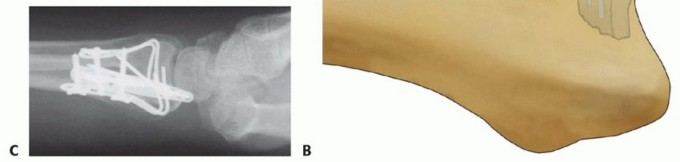

Free Articular Fragment Support with a Buttress Pin

Free articular fragments impacted into the metaphyseal cavity can be reduced and stabilized by providing support to the subchondral surface of the fragment, in combination with peripheral cortical stabilization circumferentially around the articular fragment.

In some cases, impacted free articular fragments may be adequately supported by a properly applied locking plate to provide subchondral support.

Free Articular Fragment Support with a Buttress Pin TECH FIG 13 • A. Depressed articular fragment. B. Support of free articular fragment with a buttress pin. C. Dorsal buttress pin to support fragment from endosteal surface. An alternative method is to use structural bone graft to support the free articular fragment in combination with fragment-specific fixation of the surrounding cortical shell, resulting in containment of the graft within the metaphysis.A dorsal buttress pin can also be used for direct subchondral support of impacted articular fragments. The legs of the implant are cut to length and inserted through the dorsal defect, slid distally directly behind the articular fragment, and then fixed proximally with a screw and washer. The articular fragment is sandwiched between the base of the lunate and the legs of the implant ( TECH FIG 13A-C).P.290PEARLS AND PITFALLS